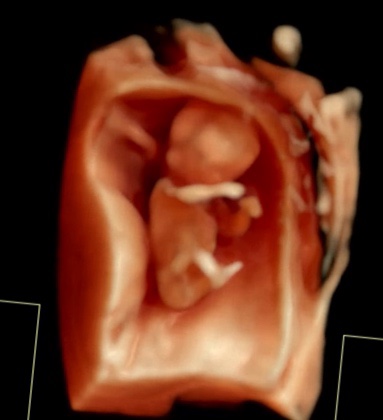

임신일기#3. 임신 11주차~임신16주차까지|태아보험 가입, 1-2차 혈액 기형아검사, 12주 정밀초음파, 입덧수액,16주 아기성별확인, 아인병원 기형아검사 결과확인

임신 11주 - 16주의 기록 임신 11주차 입덧이 여기서 더 심해질수 있나 싶었는데 더 심해짐 물 한모금 삼키...

임신일기#2. 임신 5주차~임신10주차까지|첫 심장소리, 임신주수&예정일확정, 국민행복카드발급, 8주 젤리곰 확인, 산후조리원예약, 10주차 진료

임신 5주차부터 10주차까지의 일기 입덧때매 중간중간 병원간 기록도 제대로 못했지만 .. 임신 5주차 첫 아...